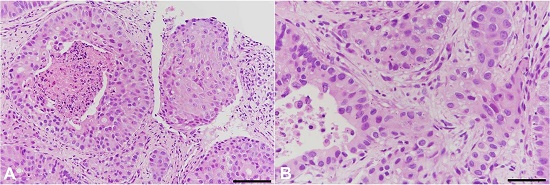

A fine needle biopsy of the right pulmonary lower lobe tumor revealed neoplastic cells with abundant eosinophilic cytoplasm and round nuclei arranged concentrically in a solid structure with central necrosis (Figure 2).

The immunohistochemical examinations were negative for thyroid transcription factor 1 (TTF-1), Napsin A, cytokeratin (CK) 5/6, and p40, but positive for CK7, polyclonal CEA (pCEA) and monoclonal CEA (mCEA), rendering the diagnosis of adenocarcinoma of unknown origin.